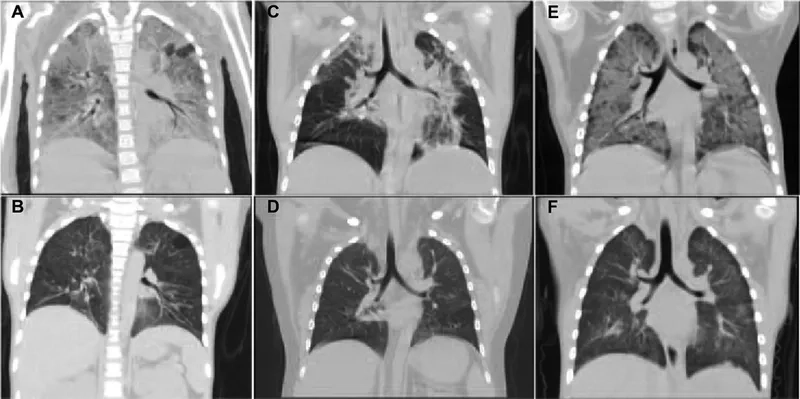

Steps in the clinical diagnosis of PCP

Image of the disease Pneumocystis Pneumonia